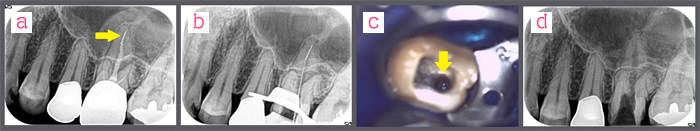

治療例《異物の除去》

根の中に閉じ込められた異物除去を他院から依頼されます。歯科用顕微鏡を使い処置します。

c.顕微鏡の映像です。光っているのが異物です。

d.除去できました。難しい処置です。

c.顕微鏡で確認します。 d.異物はとれました。

当院では、根の中の異物除去は診療報酬で認められている「根管内異物除去」という項目を使い保険診療で実施しています。

*ただし、根が破折したり除去不可能な場合は、外科的処置を行う場合もあることを承諾いただいた場合のみ実施します。